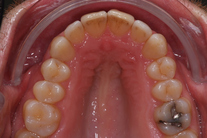

35-årig man med smal och trångställd tandbåge. Vill ha ett jämnt leende. Behandling bestod av knappt 9 månader med genomskinliga Invisalignskenor.